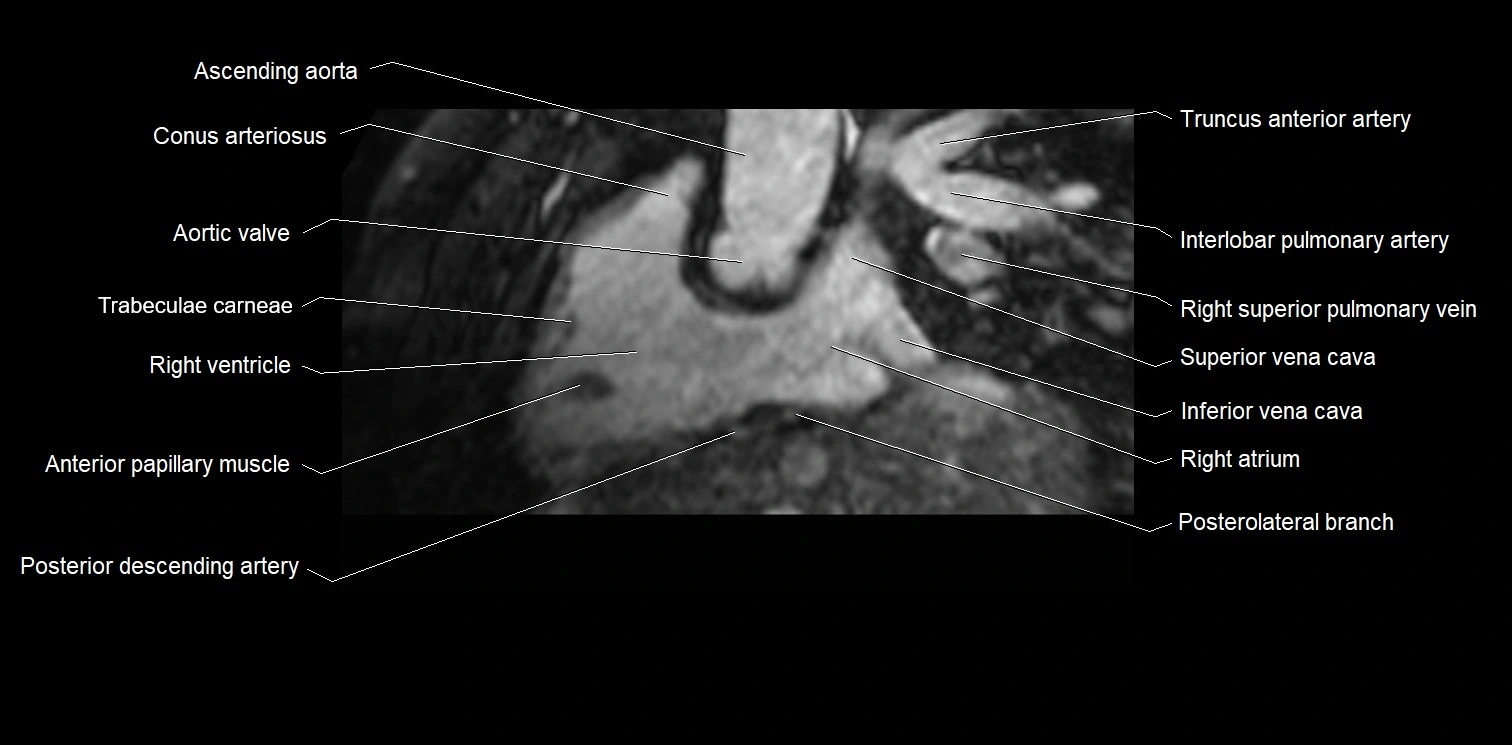

MRI image